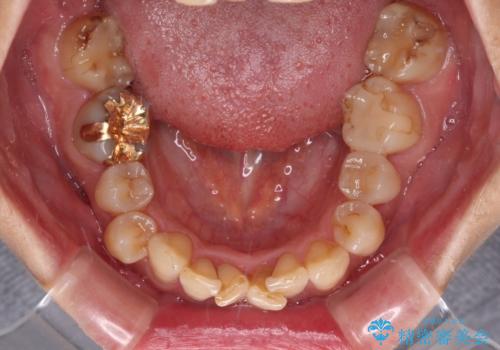

ディープバイトと前歯のデコボコ インビザラインによる矯正治療

- 前歯のディープバイトと叢生を気にして来院された患者様です。

下顎大臼歯が手前に倒れていたため、起き上がらせることで咬み合わせ高さを挙上し、ディープバイトと叢生を改善することとしました。

インビザライン特有の奥歯の噛みにくさが治療後半に発言しましたが、無事に終了させることができました。